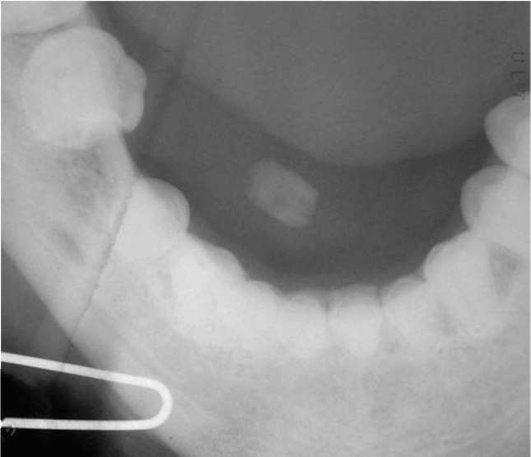

Диагностика. В распознавании слюннокаменной болезни имеет значение не только обнаружение камня, но и выявление причины камнеобразования. Анамнестический признак в виде слюнной колики в 99% случаев позволяет предположить наличие конкремента. На обзорных рентгенограммах рентгеноконтрастные камни хорошо визуализируются (рис. 6.11-6.13), на сиалограммах они видны в виде очага дефекта наполнения контрастного вещества. На эхосиалограммах камни видны по типу «звуковой дорожки». Особенно часто (более чем в 99%) камни выявляются на компьютерных томограммах.

image

Рис. 6.11. Рентгенограмма черепа в прямой проекции. В области левой околоушной железы определяется конкремент

Рис. 6.12. Рентгенограмма нижней челюсти в боковой проекции. В области левой поднижнечелюстной железы определяется конкремент

С помощью бимануальной пальпации удается определить камень в толще поднижнечелюстной железы или по ходу ее протока. Мелкие камни прощупываются только вблизи устья протока. Если камень располагается в переднем отделе околоушного протока, то он пальпируется со стороны слизистой оболочки щеки, при премассетериальной и массетериальной локализации его можно выявить со стороны кожных покровов. При бимануальной пальпации уплотнение в железе может определяться не только при наличии камня, но и при хронической инфекции, флеболитах, воспалении лимфатических узлов, амилоидозе, полиморфной аденоме. Зондирование протока позволяет выявить камень и определить расстояние до него от устья. Противопоказанием к проведению зондирования является обострение сиаладенита. Для зондирования используют специальные слюнные зонды разного диаметра. Они имеют гибкую рабочую часть и разный диаметр, что облегчает зондирование и позволяет определить диаметр устья выводного протока.

Рис. 6.13. Рентгенограмма в проекции дна полости рта. В правой подъязычной области определяется камень